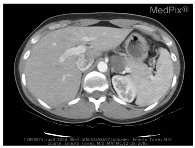

| Image | Category | Generated and Ground Truth Questions |

|---|---|---|

![]() | Abnormality | is a ring enhancing lesion present in the right lobe of the liver? is a ring enhancing lesion present in the right lobe of the liver? is the liver normal? |